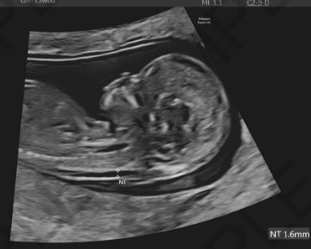

超音波検査(NT測定)

市塚清健「妊娠初期超音波計測で重要な数字」周産期医学 53(8): 1177-1180, 2023.より引用

NT(nuchal translucency) = 赤ちゃんの首の後ろのむくみ

妊娠11週0日〜13週6日の間に測定します。

エコー検査で赤ちゃんの首の後ろの透明な部分の厚さを測ります。

この厚さが3mm以上だと、染色体異常のリスクが高くなると言われています。

ただし、NT肥厚 = 異常ではありません!

正常な赤ちゃんでもNTが厚いことはあります。

そのため、NTが厚いと指摘された場合:

- 遺伝カウンセリングを受ける

- 確定的検査についての情報を提供される

- 妊娠中期に詳しいエコー検査をする